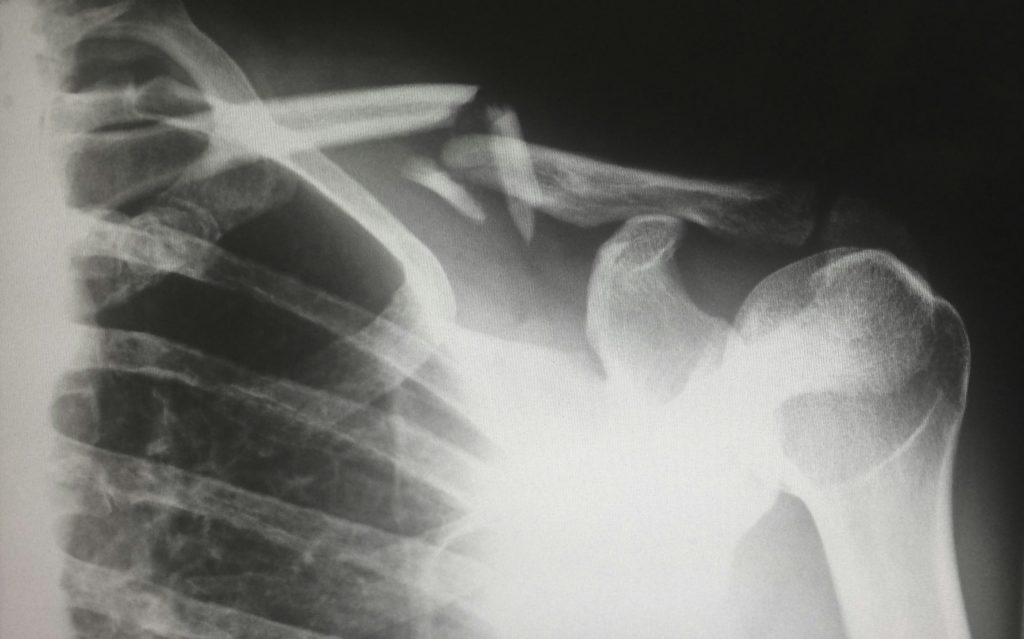

はっきりとした受傷機転があり、何をしていても痛みが強くでている

この場合は医師の診察をおすすめします。

痛みなどの症状の原因が筋肉や骨などの組織が壊れ、炎症を起こしている可能性が高いためです。

消炎鎮痛剤などのお薬が必要であったり、場合によっては骨折や脱臼、心筋梗塞などの疾患が原因であることも考えられます。